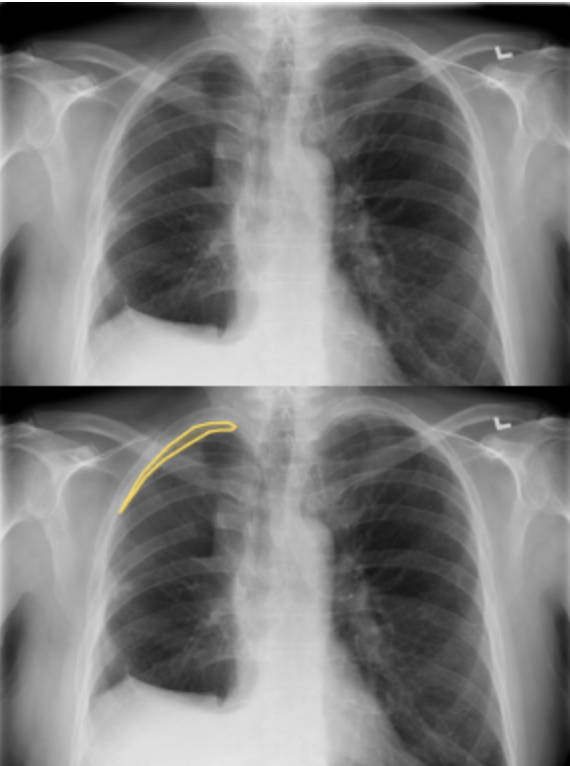

Slide 3

Here we can see on the top left side (anatomically) that we have a new area. This is causing a lack of lung lining in this location.